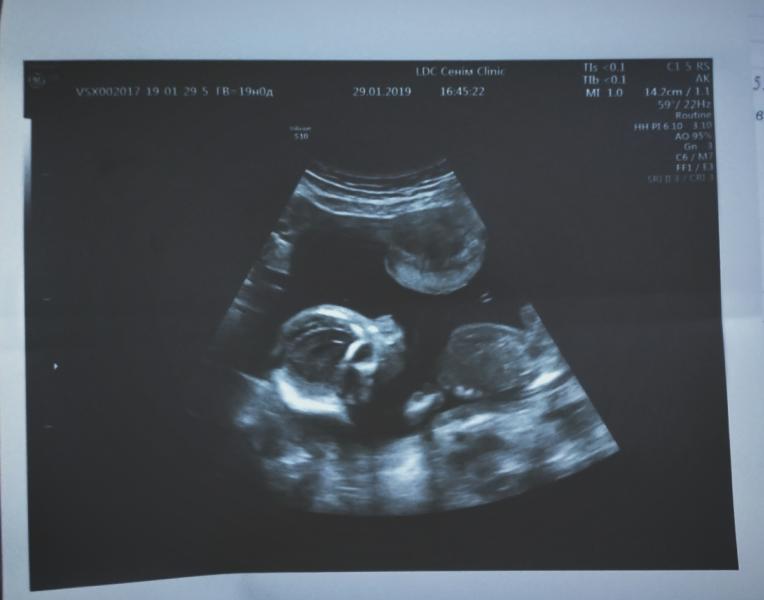

Девчат всем привет.Давно тут не появлялась.Вот Наше первое фото. Малыш растет богатырём (МашаАллах). С ним всё прекрасно.Только вот не задача,у меня вылез полный букет всяких болячек.Как сказала терапевт нафаршированная я. Подскажите как поднять иммунитет? Появился маленький токсикоз - подсела на яблоки страшно. Только красные. С нашими морозами в городе и моей нестабильной температурой тела(33.0-35.3 градуса) простудилась уже третий раз. Таблеток не пью.Боюсь этих антибиотиков.Лечусь малиной лимоном и облепихой. Да с головой. Поставили диагноз в простонародие нехватка кислорода в мозгу,плохая циркуляция крови. Прописали пирацетам сказали его можно,а другие лекарства никак все противопоказыны во время беременности. Да еще состояние душевное не очень. Кризис в семье. Не бедствуем,но во многом отказываемся. Мне бы поднять иммунитет организма,да и хватит. Боюсь за малыша. Неуклюжая стала.Руку порезала.Первые швы за 25 лет жизни.Нечего по дому делать не могу как инвалид.Муж помогает конечно сам переживает постоянно. Машину стукнула благо без последствий но тоже негатив. Короче девочки каламбур... Подскажите чем поднять восстановить иммунитет?